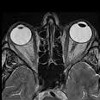

МРТ орбит и зрительных нервов

МРТ орбит и зрительных нервов. Запись многоуровневых и трехмерных изображений анатомических структур орбит путем регистрации электромагнитной реакции ядер атомов водорода. Исследование позволяет выявить все патологические процессы, локализованные в глазном яблоке, слезной железе, мышцах глаза, сетчатке, зрительном нерве, пара- и ретробульбарной ткани. МРТ тканей проводится по следующим показаниям: оценка повреждения глаз при травмах, диагностика доброкачественных и злокачественных новообразований, инородных тел, гемофтальмия, отслойка сетчатки, атрофия зрительного нерва, тромбоз сосудов сетчатки и другие патологии. Согласно справке (при исследовании сосудов и объемных образований трактов) диагноз проводится с контрастным усилением.